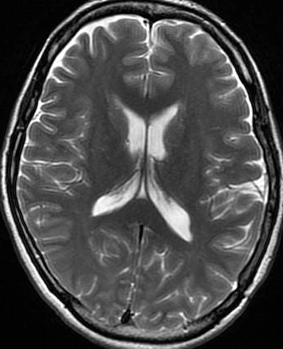

- 下のMRIは66歳の女性に脳ドックで偶然見つかった髄膜腫です.左の写真は1995年,右は2005年です。10年間で全く大きくなっていません

MRIでの髄膜腫の見え方は撮影の仕方によっていろいろです。左からT1強調画像,T2強調画像,フレア画像といいます。腫瘍の横に小さく白い領域がありますが,これは脳の腫れた部分で脳浮腫といいます。髄膜腫があると周囲に脳浮腫が生じることがあります。